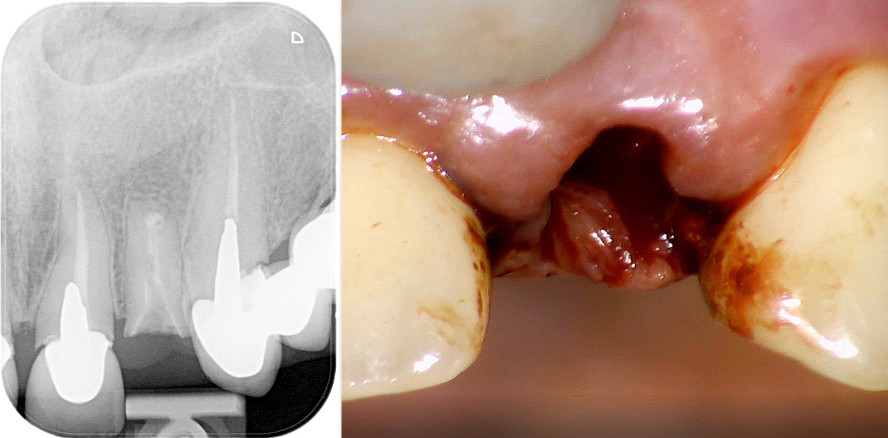

Der 50-jährige Patient konsultierte die Praxis mit einem horizontal tief fakturierten Zahn 22 (Kronenfraktur mit Verlust eines gegossenen Stiftaufbaus; Abb. 1). Wie die benachbarten Zähne 21 und 23 war auch Zahn 22 alio loco mit gegossenen Stiftaufbauten und einer Krone versorgt worden (Abb. 2). Der Fokus lag auf einer möglichst zeitnahen Therapie im Bereich des frakturierten Zahns 22. Der standardmäßigen klinischen Untersuchung schloss sich die radiologische Untersuchung an. In diesem Fall lieferte zusätzlich zur ersten Einzelzahnaufnahme ein Volumentomogramm hilfreiche Informationen für die Therapieentscheidung (Abb. 3). Die bukkale Lamelle erschien intakt. Apikal des vor längerer Zeit wurzelspitzenresezierten Zahns bot sich ein ausreichendes Knochenvolumen, um Primärstabilität apikal des Neoapex zu erzielen.

Nach einer Lokalanästhesie wurde die Zahnwurzel Regio 22 behutsam mobilisiert und extrahiert. Um das Knochentrauma zu minimieren, diente ein Periotom dem Durchtrennen der parodontalen Fasern. So konnte die Wurzel einfach und atraumatisch entfernt werden (Abb. 4 und 5). Die bukkale Knochenlamelle blieb unversehrt. Die patientenspezifischen Voraussetzungen für eine Sofortimplantation waren somit gegeben.